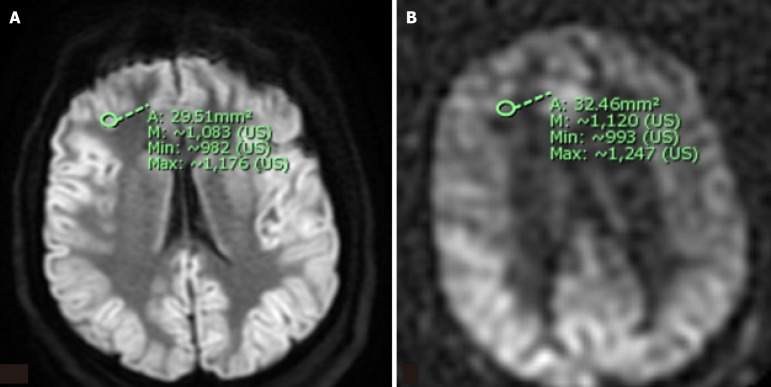

Background: Anoxic brain injury is a potentially lethal condition characterized by cerebral hypoperfusion and irreversible neuronal injury. Arterial spin-labeling (ASL) perfusion and diffusion-weighted imaging (DWI) magnetic resonance imaging (MRI) have been proposed as tools to detect cerebral ischemic changes and may aid in the assessment of anoxic injury.

Methods: We performed a retrospective review to identify patients with clinical suspicion of anoxic brain injury who underwent MRI within 15 days of cardiac arrest. Receiver operator characteristic (ROC) analysis and univariate logistic regression were used to evaluate associations between ASL perfusion scores, DWI signal intensity, and the following clinical features: (1) Myoclonus status epilepticus (MSE) within 24 hours; (2) Absent extensor or motor reflexes (EMR) at day 3 post-arrest; and (3) Absent brainstem reflexes (BSR) within 15 days.

Results: Twenty-eight patients met inclusion criteria. Increased ASL signal in the left occipital lobe was significantly associated with MSE (P = 0.038), while a trend was observed between right frontal ASL signal and EMR (P = 0.078). ROC analysis showed that ASL scores ≥ 7 were associated with higher odds of absent BSR (OR 2.14, P = 0.53), though this did not reach statistical significance. DWI signal intensity did not show significant associations with clinical outcomes. The overall discriminatory performance of ASL for predicting outcomes was limited (AUC ≈ 0.52).

Conclusion: This exploratory study suggests that regional ASL hyperperfusion, particularly in the left occipital and right frontal lobes, may be associated with adverse clinical signs following cardiac arrest. However, most findings did not reach statistical significance, and the study was underpowered to detect small-to-moderate effects. These preliminary results should be interpreted with caution and considered hypothesis-generating. Larger, prospective studies are warranted to clarify the prognostic value of ASL perfusion imaging in anoxic brain injury.